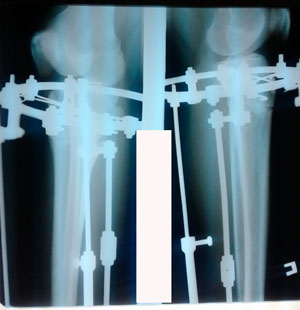

перед крутками

image-28-03-20-10-49-1.jpg